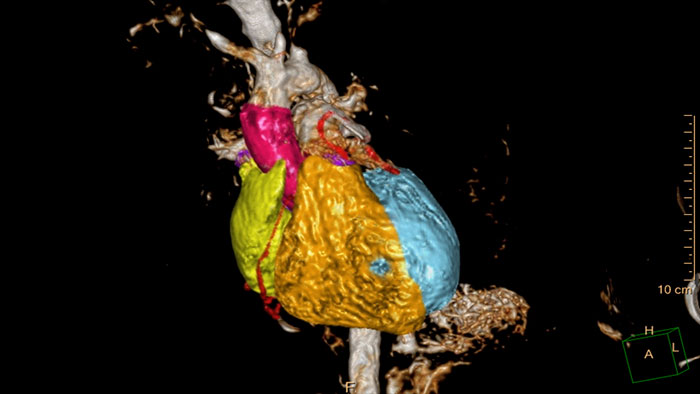

- Cardiac Whole Heart

MR Cardiac Whole Heart

Detailed 3D visualization of the segmented heart

Allows 3D visualization of the heart and vessels anatomy on T1 3D or MRA acquisition. Manual editing tools as well as semi-automatic tools based on seed- and mask-based segmentation can be used as well as full automatic model-based heart segmentation.

Benefits

- The segmentation can be manually corrected with editing tools until the user has reached the defined image details.

- The 3D visualization can be saved with a batch tool or the user can create and export the segmented objects in VTK or STL format.